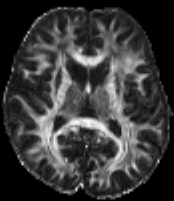

The super resolution image in 6(a), serving as a reference here, was obtained using the super-resolution reconstruction technique that combines multiple thick-slice DWI with all 60 diffusion directions into a high-resolution image, cf. (citep \@BBN(Ramos-Llordén et al., 2020)). This technique yields a high quality image with good detail preservation, but takes much longer scan time than the standard upsampling method in 6(c), where the FA map of the low-resolution data was up-sampled using 3DSlicer (citep \@BBN(Fedorov et al., 2012)) to the higher resolution.

The image in 6(b), cf. (citep \@BBN(Ning et al., 2016)), was obtained using a combined super-resolution reconstruction, compressive sensing, and spatial regularization techniques with thick-slice images, where each thick-slice DWI has a different set of 20202020 diffusion gradient directions, saving indispensable scan time. The advanced method yields a much higher visual quality image than 6(c), preserving more anatomical details.

Refer to caption

(a) Reference

(b) (17.62, 0.57, 0.19)

(c) (18.23, 0.58, 0.26)

Figure 6: Visualized FA images obtained from diffusion MRI with super-resolution reconstructions. The up-sampled image (c) with lower resolution is wrongly judged to have better quality than the high-resolution reconstruction (b) by PSNR and SSIM, LPIPS judges this task correctly.

FR-IQA mismatch

We can see in Figure 6 that PSNR and SSIM misjudge the visual quality of the high-resolution reconstruction in (b) in comparison to the up-sampled image in (c). The image is per default more blurry and does not provide sufficient anatomical details and therefore offers worse visual quality than the reconstruction in (b). LPIPS yields more sufficient results in this example, and correctly attributes (c) a higher quality error.

In this example, it has to be noted that the computed IQA numbers are generally quite low, because the resulting FA images do not necessarily have the same range or distribution as the reference image. Therefore, in order to compare the reconstruction quality directly, this task generally benefits from NR-IQA evaluation.